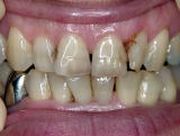

小さいものから、全部被せるものまでありましたが、ご希望通りの金属なしの治療を終了いたしました。患者様にもこの写真をお渡ししまして、比較をしていただきました。

銀歯を白くしたいとのご希望でした。

銀歯と白い葉では印象が全く違います。非常に明るく感じます。

下の歯は会話中や笑ったときに奥歯まで見えますので、白くする効果は十分あります。